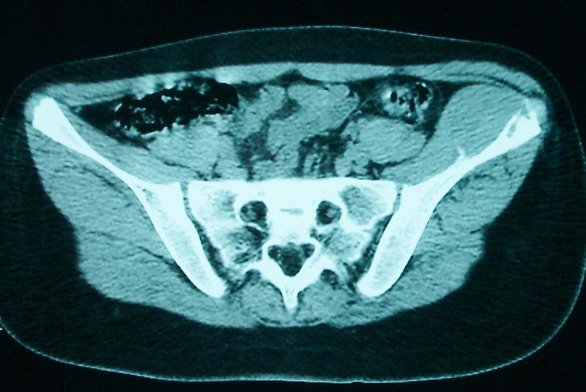

女 13岁 4月前有臀部肌肉注射史 3月前发热 最高体温38.5 2月前出现左髂骨疼痛 不剧烈能忍受 发热时高时低 按感冒治疗无好转 近日左髂骨疼痛加重 一星期前wbc 12.2 今日wbc9.5

左侧髂骨溶骨性骨质破坏,骨皮质侵蚀,灶周可见软组织肿块,支持考虑骨肉瘤可能性大。

髓腔起源,弥漫性溶骨性骨质破坏并软组织肿块,膨胀不明显,无显著钙化及瘤骨,有骨膜反应,结合年龄考虑恶性,尤文氏肉瘤可能性大。

鉴别:尤文氏肉瘤>毛细血管扩张型骨肉瘤>骨原发淋巴瘤>朗格罕氏细胞增生症>软黏纤>慢性骨髓炎>tb。